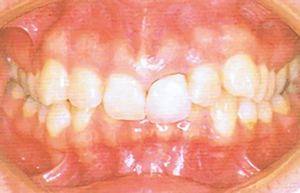

type03

• 上の前歯が下の前歯よりも、ひどく前に出ている

• 上唇が上ったままで、口を閉じにくい

• 無理して口を閉じると、口元が不自然に歪む

「上顎前突(じょうがくぜんとつ)」である可能性があります。一般的には「出っ歯」と呼ばれます。前歯の角度異常、上顎が成長し過ぎている、下顎の成長不足、指しゃぶりの癖等が原因です。また、発育過程で鼻に疾患を抱え、口呼吸になっている子どもにも多く見られる症状です。